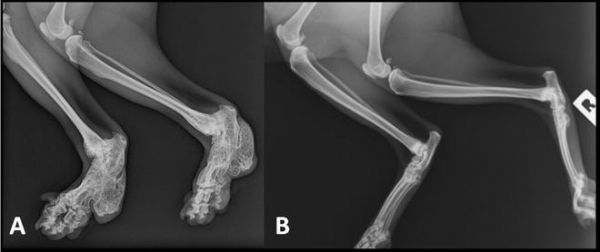

据兽医介绍,患病的折耳猫四肢肿大而僵硬,尾巴变粗,尾椎骨中上段出现弯曲,关节僵硬,活力明显下降。症状严重的折耳猫基本不活动,经常像人类一样坐立,稍微按压后肢会有疼痛感,有些甚至生活不能自理,这给宠物猫、宠物主带来了极大的伤害。